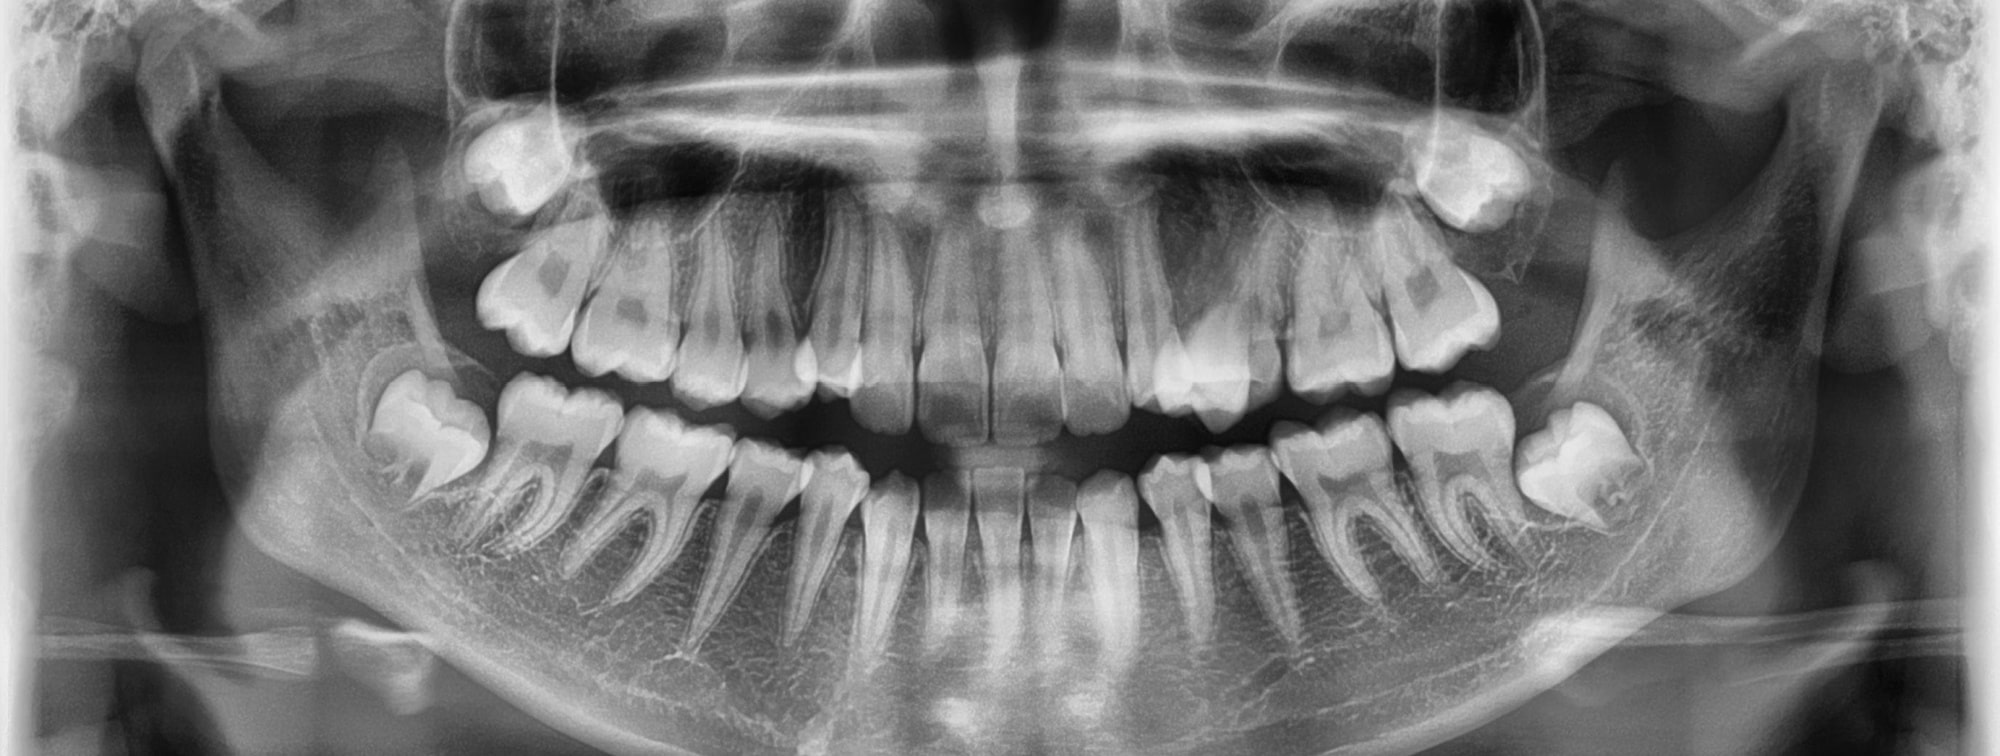

Wisdom teeth removal is a very common procedure for individuals aged 17-25. These are the last permanent teeth to appear and usually, one or more wisdom teeth are removed at a time. The need for wisdom teeth removal can often be detected by X-Rays or the patient themselves might notice pain or discomfort first. When you contact Sekhon Family Dentistry, our experienced staff can help you with all your wisdom teeth removal needs in the Carlington, Ottawa area.

In total, your wisdom teeth removal surgery should take approximately 45 minutes and you will be placed under a form of anesthesia. During your initial consultation, you can ask which type of anesthesia your dentist or oral surgeon plans on using for your procedure. It could be local, IV sedation, or general anesthesia. During the surgery itself, your dentist or oral surgeon will make incisions in the gum tissue to expose and gain access to the tooth and bone. Here they will remove the tooth, clear the area afterward of debris, tooth, or bone, and stitch the area back up.